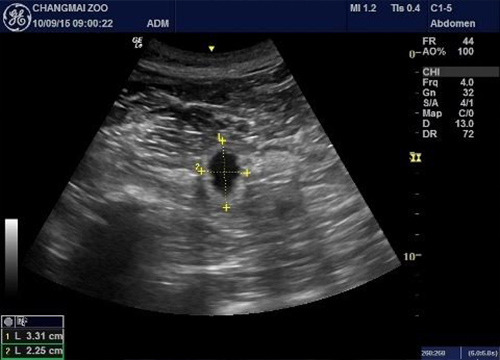

สวนสัตว์เชียงใหม่ร่วมกับองค์การสวนสัตว์ฯ แถลงยืนยัน หลินฮุ่ย ตั้งท้องจริง เผยภาพอัลตราซาวด์พบโครงสร้างตัวอ่อนในมดลูกชัดเจน ขณะทีมพี่เลี้ยงติดตามพฤติกรรมใกล้ชิดตลอด 24 ชั่วโมง

เมื่อวันที่ 11 กันยายน 2558 ผู้สื่อข่าวรายงานว่า ที่สวนสัตว์เชียงใหม่ นายเบญจพล นาคประเสริฐ ผอ.องค์การสวนสัตว์ พร้อมด้วยหัวหน้าโครงการวิจัยและจัดแสดงหมีแพนด้าในประเทศไทย, ผู้เชี่ยวชาญด้านระบบสืบพันธุ์ และนายนิพนธ์ วิชัยรัตน์ รักษาการ ผอ.สวนสัตว์เชียงใหม่ ร่วมกันแถลงผลการตรวจสุขภาพและอัลตราซาวด์หมีแพนด้าหลินฮุ่ย 2 ครั้ง ในรอบ 24 ชั่วโมงที่ผ่านมา พบว่า การอัลตราซาวด์ครั้งแรก พบมีถุงหุ้มตัวอ่อนอย่างชัดเจน ส่วนการอัลตราซาวด์ครั้งที่ 2 พบมีลักษณะโครงสร้างคล้ายตัวอ่อนอยู่ในผนังมดลูก ซึ่งคล้ายกับแพนด้าที่ตั้งท้องจริงทั่วไป

ทั้งนี้ จะต้องติดตามดูพัฒนาการกันเรื่อย ๆ ว่าจะมีสัญญาณชีพและคลอดปกติหรือไม่ เนื่องจากแพนด้าเป็นสัตว์ที่ยากจะคาดการณ์ได้ และอาจมีการดูดกลับของตัวอ่อนได้เช่นกัน อย่างไรก็ตาม ทีมพี่เลี้ยงจะดูและติดตามพฤติกรรมของหลินฮุ่ยอย่างใกล้ชิดตลอด 24 ชั่วโมงต่อไป